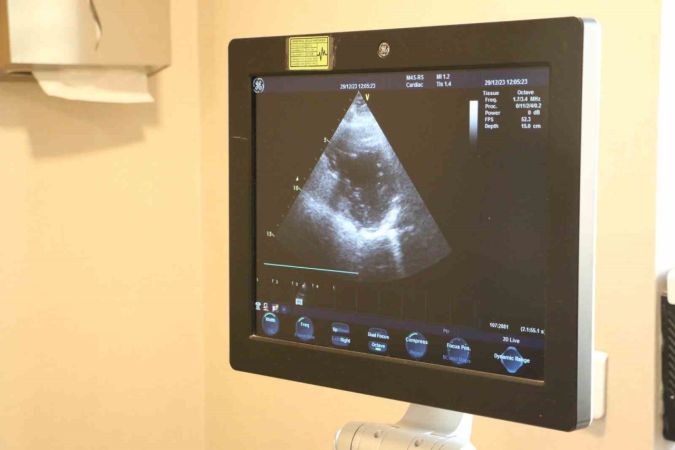

Kalp kapak hastalığı tanısı alan bireylerin düzenli takibi ve gerektiğinde cerrahi müdahale önem taşımaktadır. Dr. Akçalı, hastaların ağır sporlardan kaçınmaları gerektiğini ve düzenli kardiyolojik takip gerekliliğini belirtiyor. Kalp kapak hastalığı olan vatandaşların ileri efor sarf eden sporlardan uzak durmaları gerektiği ifade ediliyor.